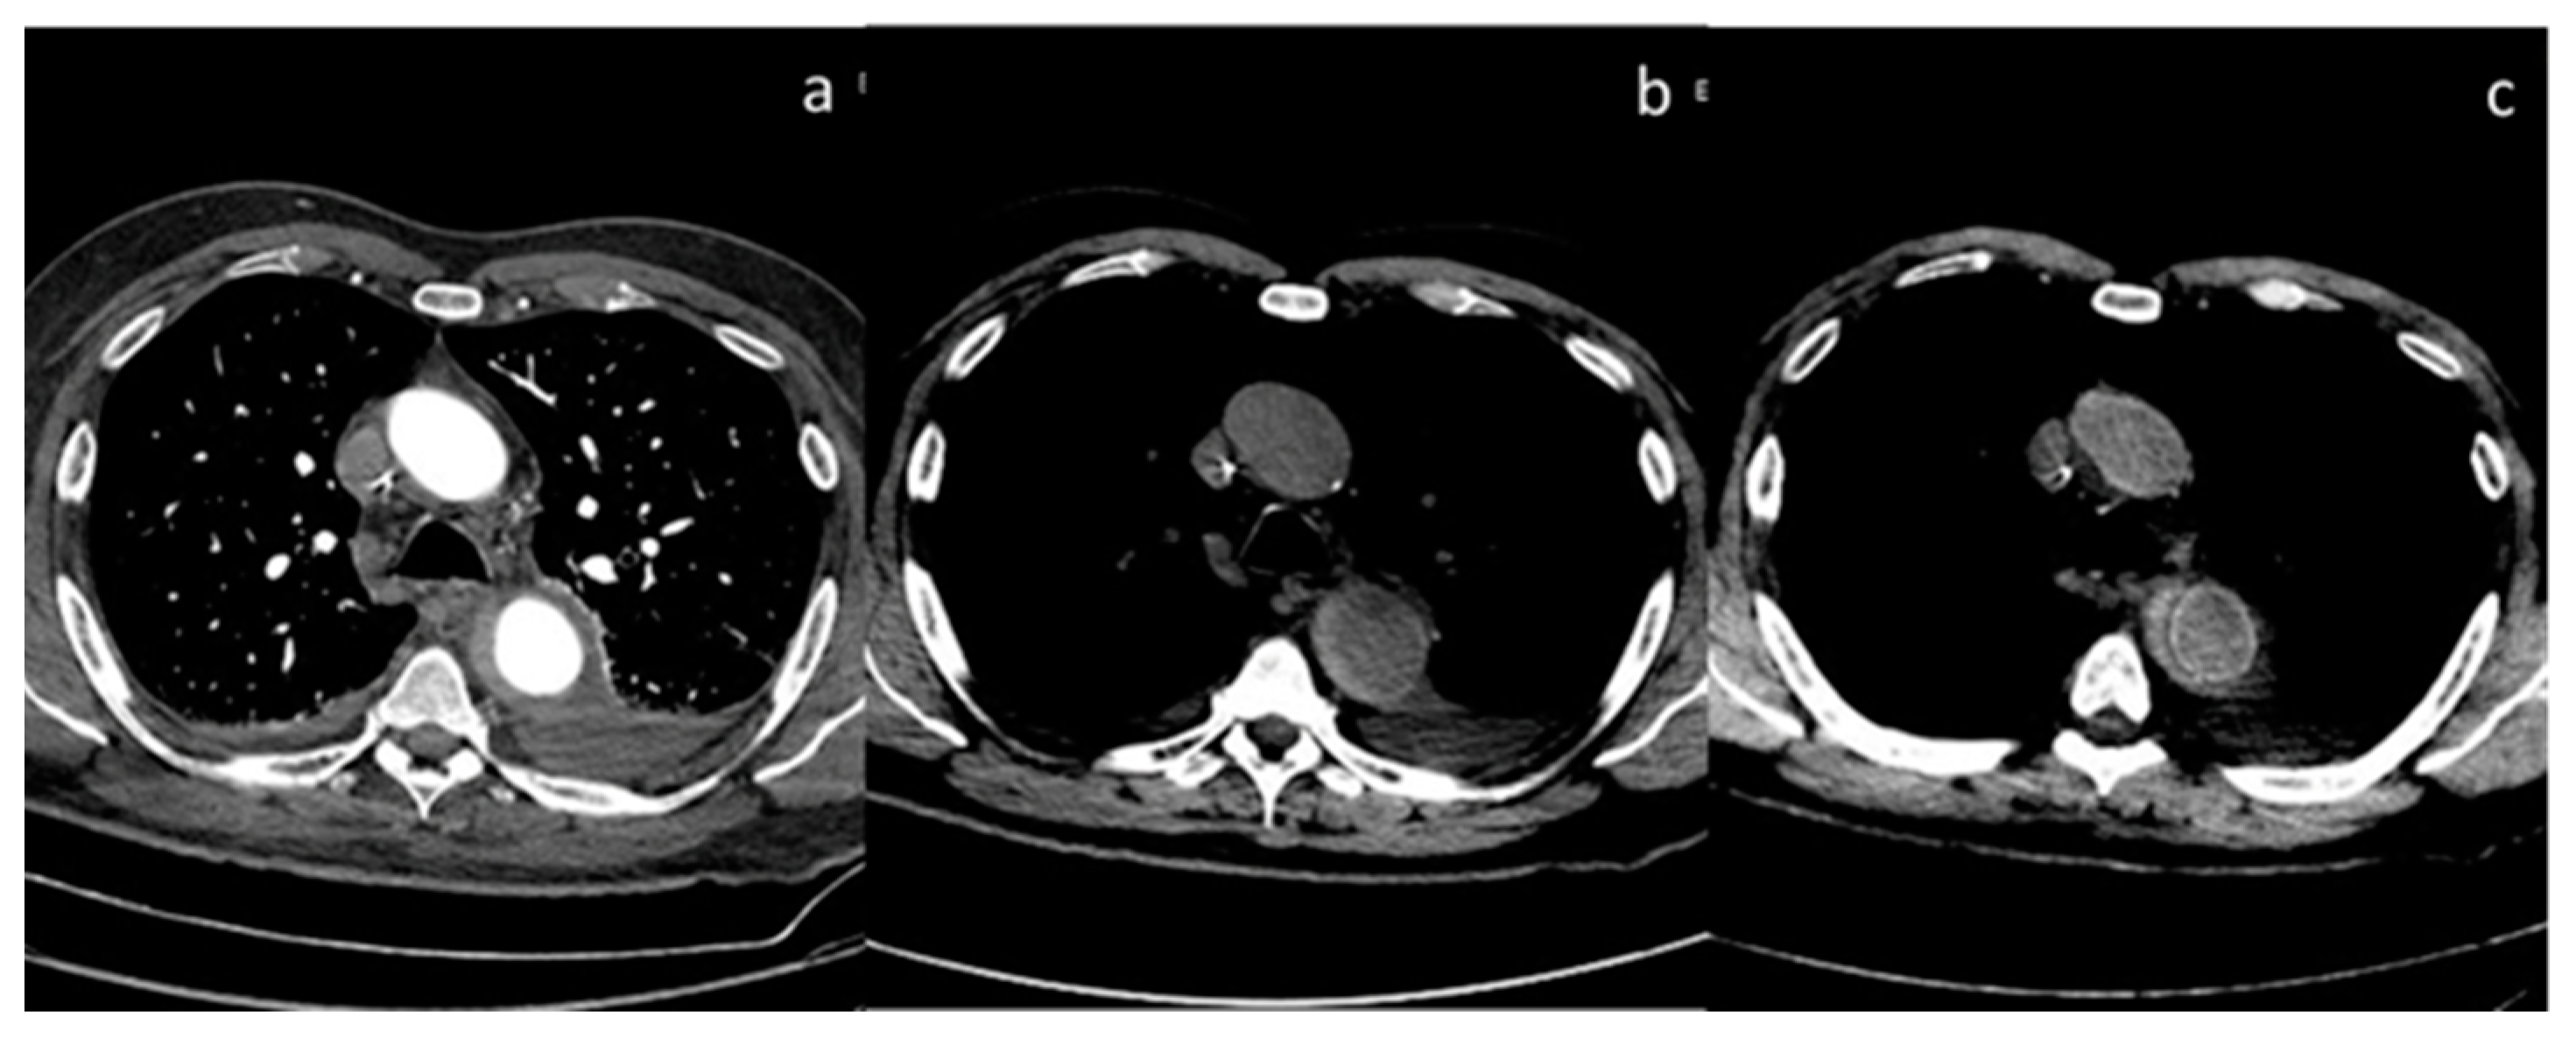

- Si-Mohamed, S.; Dupuis, N.; Tatard-Leitman, V.; Rotzinger, D.; Boccalini, S.; Dion, M.; Vlassenbroek, A.; Coulon, P.; Yagil, Y.; Shapira, N.; et al. Virtual versus true non-contrast dual-energy CT imaging for the diagnosis of aortic intramural hematoma. Eur. Radiol. 2019, 29, 6762–6771. [Google Scholar] [CrossRef] [PubMed]

| Si-Mohamed et al. [67] Retrospective study | France | To assess whether VNC images derived from contrast dual-layer DECT images could replace TNC images for aortic intramural hematoma diagnosis in acute aortic syndrome imaging protocols by performing quantitative as well as qualitative phantom and clinical studies. | 21 | IQon, Philips Healthcare No C.I. | Dual-layer -DECT offers similar performances with VNC and TNC images for intramural hematoma diagnosis without compromise in diagnostic image quality. VNC imaging with dual-layer DECT reduces the number of acquisitions and radiation exposure in acute aortic syndrome imaging protocol. |